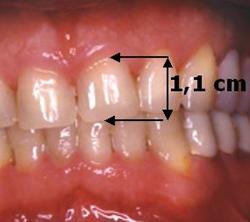

Absence de visibilité des dents supérieures lors du sourire forcé

L'espace de repos est très important. La lèvre supérieure est tombante

Cette augmentation de la DVO des secteurs postérieurs devra permettre d'obtenir au niveau antérieur une longueur de l'incisive centrale de 11 mm.

Idéalement, la longueur de l'incisive centrale doit être de 11 mm.